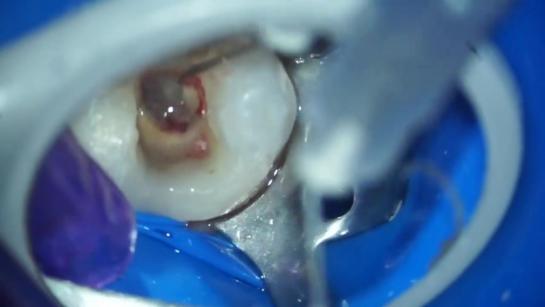

Детская стоматология by Видео для стоматологов Videos 3:40 10:24 2:46 4:52 0:44 6:33 4:58 4:41 0:56 0:58 0:49 0:26 62:39 63:40 43:44 53:41 78:09 18:52 2:50 60:04 2:26 63:48 28:49 68:25 38:18 83:51